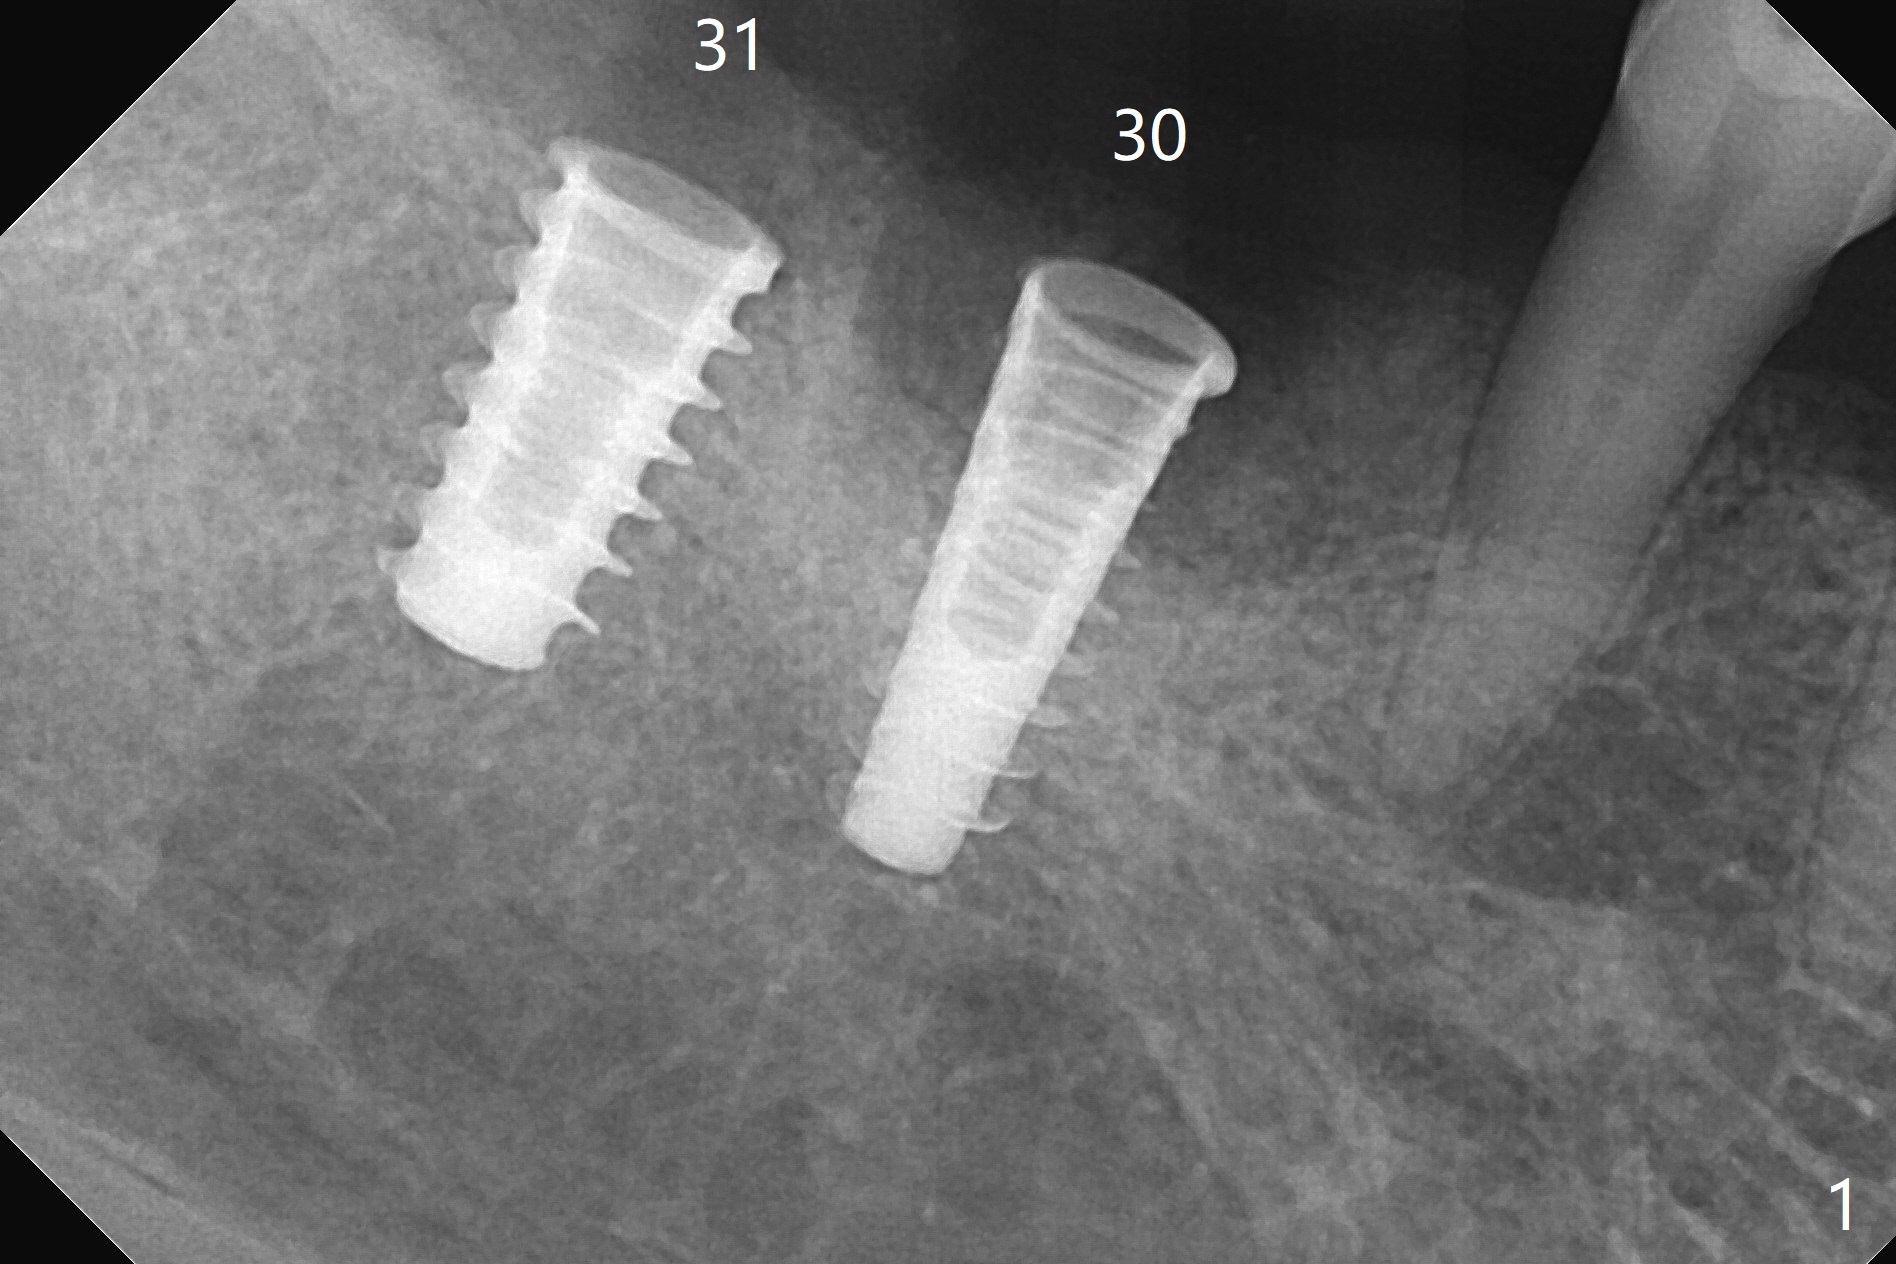

Following osteotomy, 4.5x11 and 5x9 mm dummy implants are placed at the sites of #30 and 31, respectively (Fig.1). Due to limited inventory of Magicore and patient's in-cooperation, FC implants (4.5x9 and 5x9 mm) are placed (Fig.2). A healing abutment (6x4 mm) is placed at #31 because of low torque (overprep), while a pair abutment (6.5x5.7(4) mm) is placed at #30. Vera Graft is placed with autogenous bone (*). The implant/abutment ratio at #30 is unfavorable. If the implant turns out to be loose, immediate implant should be larger in the future. Note bone growth, especially at #30, 2.5 and 4 months postop (Fig.3,4). In fact the abutments are incompletely seated. The crown of #30 is loose 2 years 8 months post cementation, while the abutment at #31 remains incompletely seated (Fig.5). The latter is completely reseated after separating the crown, while a smaller one is seated at #30 (Fig.6) due to use of a small healing abutment earlier (Fig.5). A good piece of news is the presence of the bone between the implants (Fig.5,6 *), which contributes to interimplant papilla. Return to Lower Molar Immediate Implant, Prevent Molar Periimplantitis (Protocols, Table), IBS77, 2-5 Xin Wei, DDS, PhD, MS 1st edition 09/22/2017, last revision 12/01/2020